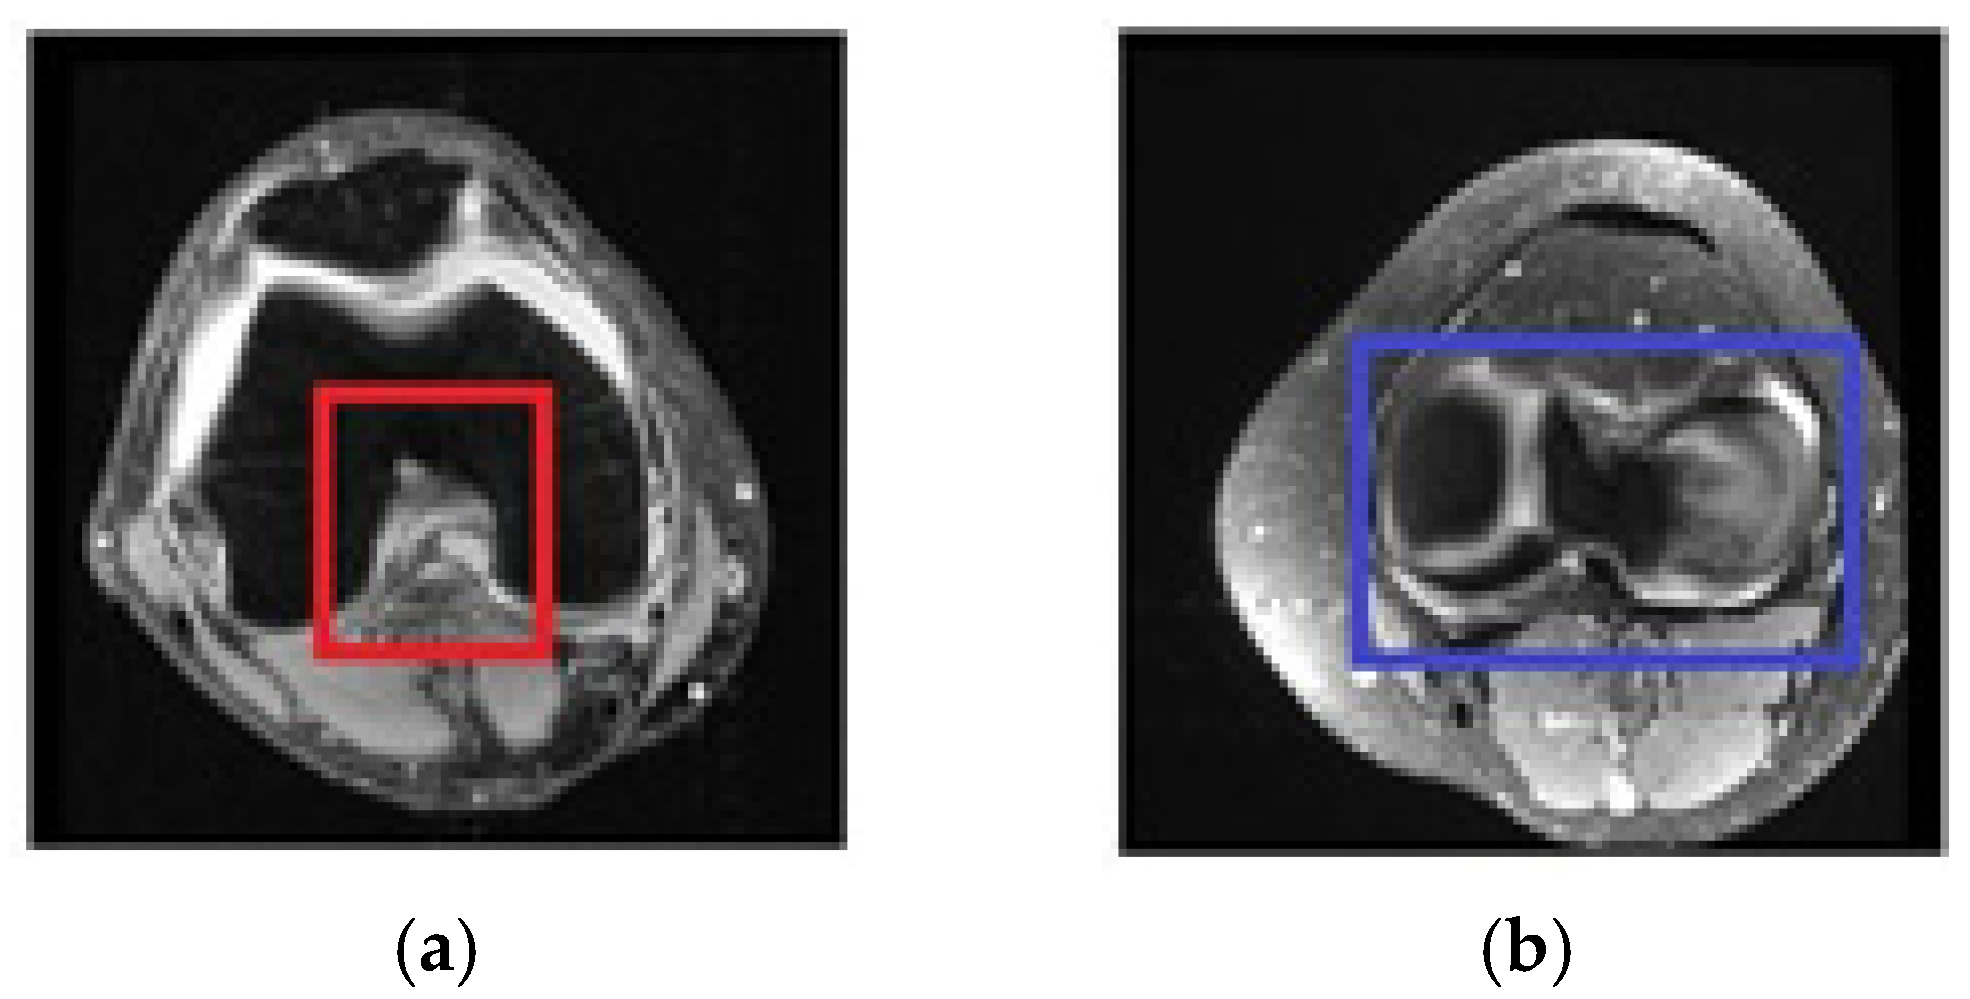

2.4. Selecting the Relevant Area

2.4.1. Selecting Relevant Areas on the Sagittal Axis

2.4.2. Selecting Relevant Regions on the Coronal Axis

2.4.3. Selecting Relevant Regions on the Axial Axis

2.4.4. Structure of the Region of Interest Model